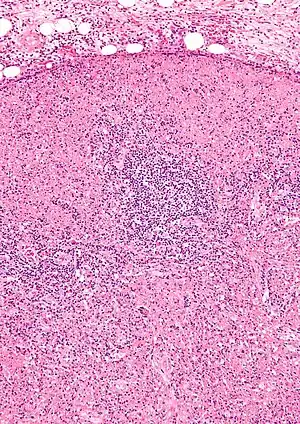

| Micrograph of a lymph node with Kikuchi disease showing the characteristic features (abundant histiocytes, necrosis without neutrophils). H&E stain. | |